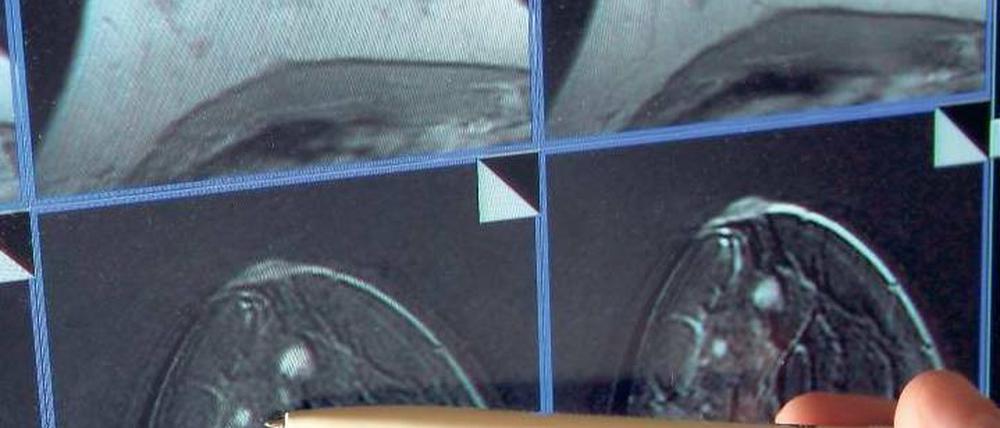

Medizin: Kampf gegen Krebs

Die Behandlung der Volkskrankheit könnte oft besser sein. Der Nationale Krebsplan soll dazu beitragen - nun liegt er dem Bundestag zum Beschluss vor.